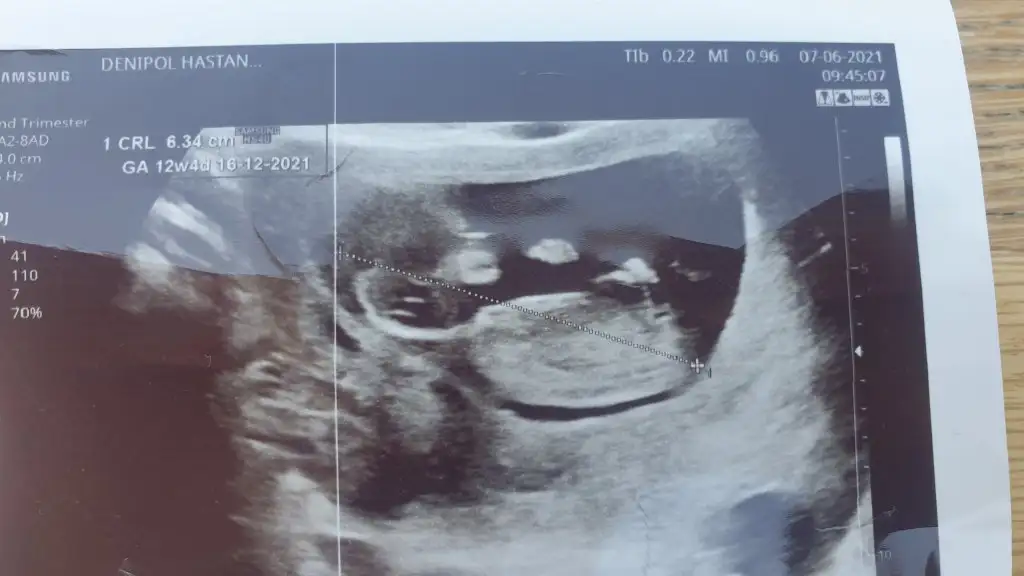

Teyzoşları bize de tahmin yapar mısınız doktorumuz yoğun ısrarımızla bacak arasına bakıp bi tahmin yürüttü ama sakın alışveriş felan yapma değişebilir diye tembihledi beni yine de merak ediyorum 😇

Merhaba İkra Meyra, 2021 Aralık ayı annelerinde sizin tahmin yaptığınız söyleniyor =)

12 Mayıs'ta kalp atışını duyduğum gün, karından, şimdi 10 haftayız.

Tahmin rica etsem ??